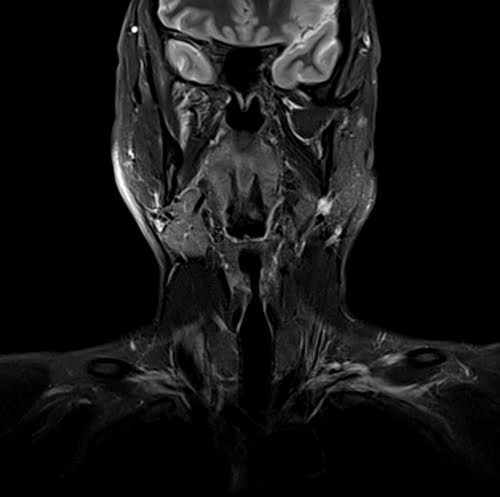

Neck MRI coronal STIR images